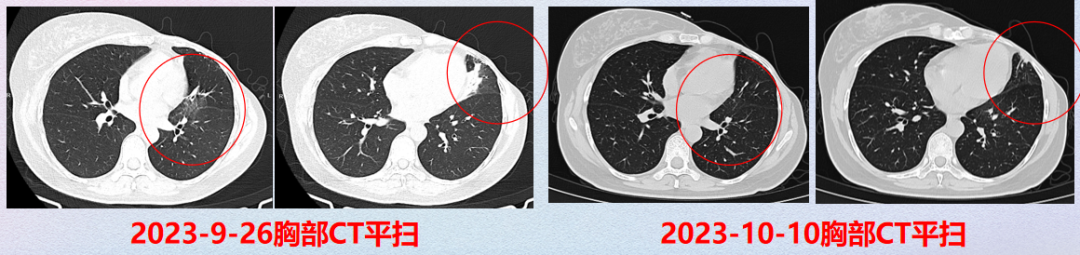

2023年9月

患者出现咳嗽,咳白痰,遂完善胸部CT检查(2023.09.26),提示两肺炎症,首先考虑感染性,遂予莫西沙星经验性抗感染治疗、暂停T-DXd治疗;2周后复查胸部CT,肺部炎症较前好转,遂继续予T-DXd治疗。